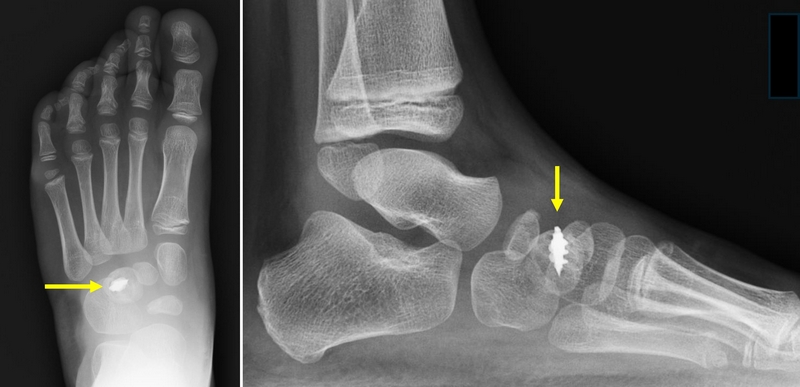

Our minimally invasive procedure involves fixing the transfer tendon with a screw anchor inserted into the bone. This screw is embedded in the bone (therefore, it does not need to be removed) and ensures immediate stability during the procedure.

The tibialis anterior is the muscle that allows you to lift your foot upward while walking. In patients with recurrent clubfoot, this muscle works incorrectly, causing the foot to roll inward.

The tibialis anterior transfer changes the action of this muscle so that it can work more effectively and turn the foot outward instead of inward.